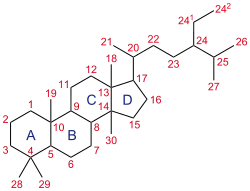

This is a list of progestogens that are or that have been used in clinical or veterinary medicine. They are steroids and include derivatives of progesterone and testosterone.

Testosterone derivatives

| Compound | Chemical name(s) | Structure |

| Testosterone | 17β-Deacetyl-17β-hydroxyprogesterone Androst-4-en-17β-ol-3-one |

Testosterone itself does not have significant progestogenic activity. Testosterone is instead classified as an anabolic-androgenic steroid and is included here purely because it is the parent structure of this group of progestins.